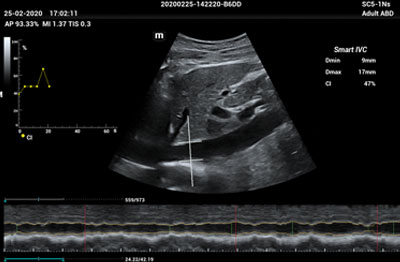

The ME8 Ultrasound System has been thoughtfully designed to overcome the obstacles clinicians face in today’s challenging healthcare environment. Powered by our groundbreaking software-based beamformer technology, ZONE Sonography® Technology+(ZST+), the ME8 Ultrasound System empowers decision-making by providing end-users best-in-class image quality and access to a comprehensive suite of workflow enhancement tools.